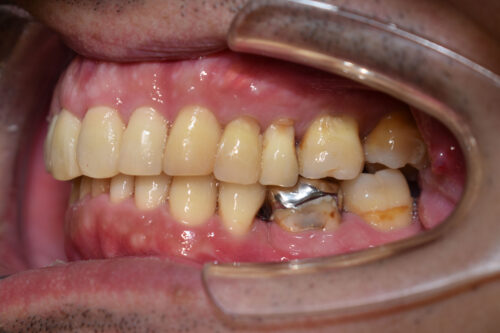

初診時年齢 39歳 男性

歯のでこぼこ(叢生)

下顎左側第二小臼歯欠損

出っ歯

本症例も

上下とも歯が唇側に傾斜し

出っ歯も呈しておりました。